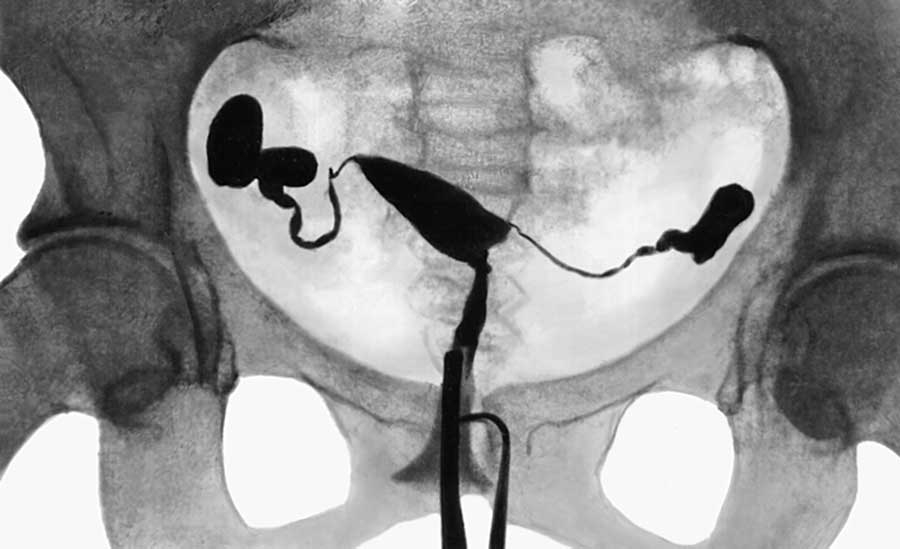

Гистеросальпингографией (ГСГ) или метросальпингографией (МСГ) называется диагностическое исследование проходимости фаллопиевых труб и изучение их состояния. Этот метод представляет собой проведение рентгена с дополнительными манипуляциями. Процедуру выполняют сразу два врача: рентгенолог и гинеколог. Врач вводит в полость матки катетер, через него поступает контрастное вещество. Способность вещества проникнуть через трубы в брюшную полость говорит о степени их проходимости.

ГСГ маточных труб — один из самых информативных вариантов обследования. Диагностика показывает точные результаты, что дает возможность сразу же опровергнуть или подтвердить бесплодие, а также некоторые другие проблемы.

Основное преимущество гистеросальпинографии — высокая информативность, так как контрастная жидкость четко видна на снимках. К тому же после процедуры у пациентки они на руках остаются снимки, с которыми можно обратиться к другому специалисту в любое время.

Как правило, за время проведения процедуры делают от 4 до 6 снимков. Вначале фиксируется состояние матки. Затем в полость подают еще 4 мл контрастного вещества, что позволяет более четко осмотреть придатки. Если этого объема жидкости недостаточно, то вводят столько, сколько необходимо. После того как жидкость заполнит орган, она устремляется в трубы. Если на изображении видно, что раствор вышел в брюшную полость с обеих сторон, то трубы проходимы. Если же нет, то можно увидеть, на каком участке жидкость остановилась.